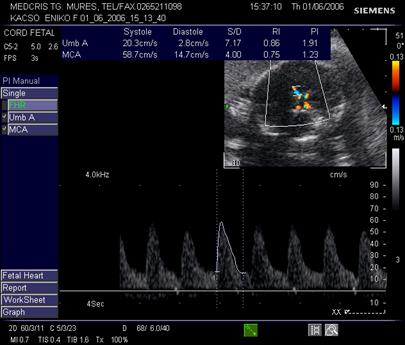

Doppler in circulatia cerebrala

Creierul fetal primeste circa 40% din debitul cardiac total. Cele 3 scurtcircuite ale aparatului fetal cardio-vascular: canalul arterial, ductul venos si foramen ovale, permit devierea sangelui bine oxigenat spre creier, cord si suprarenale, in caz de hipoxie (teritorii privilegiate).

Daca cresterea tensiunii arteriale si a frecventei cardiace din cadrul hipoxiei fetale, sunt consumatoare mari de oxigen si autolimitate, redistribuirea fluxului de sange se face prin vasodilatatie compensatorie in "teritoriile privilegiate."

Artera cerebrala medie are directia inainte si in afara, primeste sange din carotide si arterele vertebrale. Planul de reperare este cel al pedunculilor cerebrali, lateral de poligonul Willis. Ea reprezinta sediul preferat pentru velocimetria cerebrala.

In sarcina normala, rezistenta crescuta cerebrala se traduce in velocimetria cerebrala prin diastola scazuta. Aspectul normal al velocimetriei cerebrale permite aprecierea unei stari de bine fetale pentru 2 saptamani [17].

Indicele Arbeille (raport cerebro-placentar) = IR a. cerebrala medie/IR a. ombilicala este supraunitar in conditii de sarcina fiziologica.

In afara fenomenelor de redistribuire a fluxurilor vasculare fetale, amplitudinea vitezelor diastolice la arterele cerebrale ramane inferioara fata de artera ombilicala, deci valoarea indicelui cerebroplacentar este supraunitara. Vasodilatatia cerebrala din redistribuirea fluxurilor sanguine, din suferinta fetala cronica, va determina o scadere semnificativa a IR cerebrala, cu trecerea indicelui cerebroplacentar in valoare subunitara.

Fig. nr.325. Doppler normal pe a. cerebrala medie , la 27 sapt.